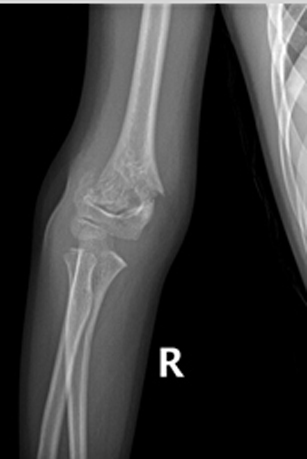

2018年6月2日,关节外科-创伤骨科底垚宗主治医师小儿的骨科门诊接诊一名12岁肘关节损伤患儿,完善相关检查后X线提示:右肱骨髁上骨折。

患儿,李XX,男性,12岁,主因“摔伤右肘疼痛、畸形、活动受限1天余”门诊入院。小儿肱骨髁上骨折根据Gartland分类法,分为I型无移位;II型有移位但后侧皮质完整;III型有移位且无骨皮质接触。此患者骨折分型为III型骨折,骨折移位通过外固定维持骨折位置困难,手术指征明确。入院后积极术前准备,于2018年6月5日行手术治疗,术中给予外侧三枚克氏针、内侧一枚克氏针固定,见骨折位置满意,术后石膏固定。

1.jpg术前